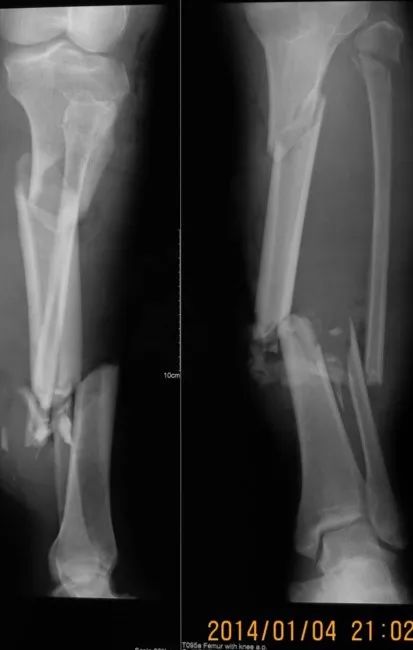

下面1例是我的学生所发。病史清楚,跗骨骨折后伤口开放,每次换药用双氧水冲洗伤口,造成骨坏死

跗骨感染

该例患者需要汲取的经验和教训:不要使用双氧水冲洗伤口死骨密度高是因为不参与代谢周围骨疏松治疗清理死骨后用骨水泥诱发诱导模反复几次做半开放植骨手术后走路刺激骨愈合,改善骨质愈合。